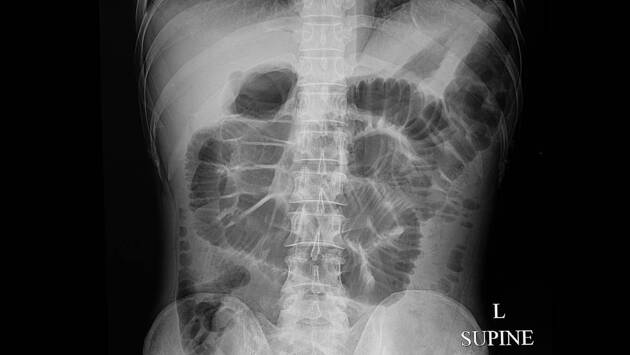

«Сначала у меня было вздутие живота, спазмы, но я списала это на синдром раздраженного кишечника. Иногда я видела кровь на туалетной бумаге, но подумала, что это из-за развившегося после родов геморроя. Я чувствовала себя уставшей, но считала это нормальным, так как у меня был напряженный график», — назвала пациентка первые симптомы заболевания.

Также доктор обратила внимание на то, что рак кишечника также могут сопровождать боль в животе, вздутие, необъяснимая потеря веса и беспричинная усталость.

Когда у нее начались проблемы с дефекацией, она наконец отправилась к врачу. После нескольких обследований у нее выявили рак кишечника. Патель перенесла операцию по удалению опухоли и многомесячную химиотерапию.